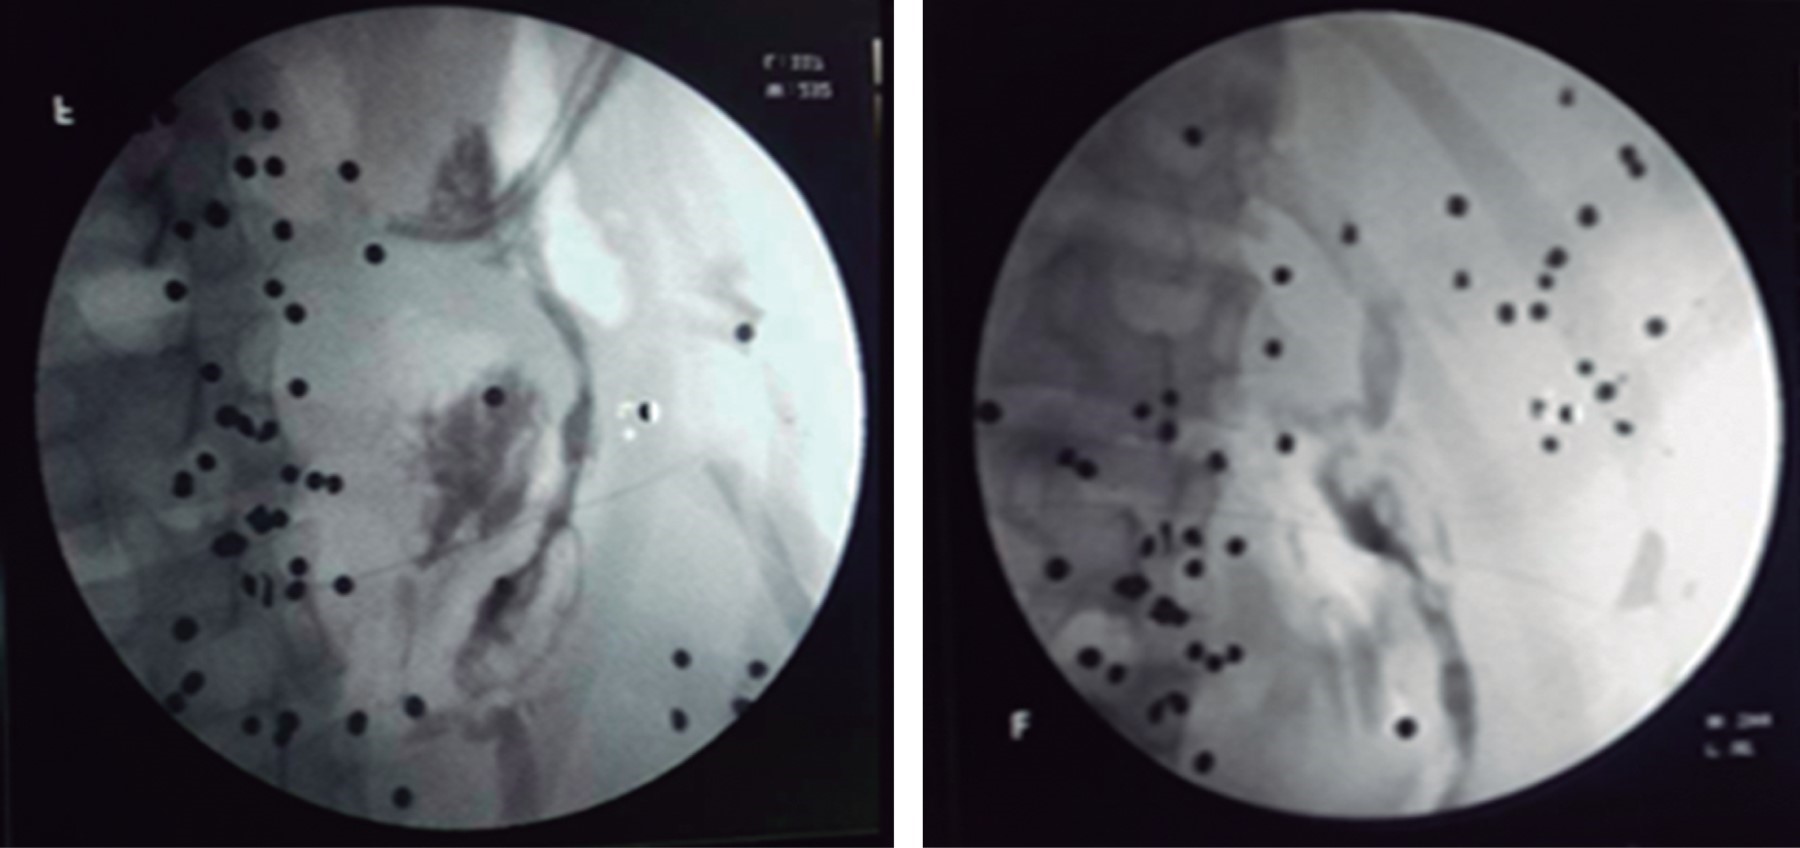

Control postoperatorio: se realiza fistulografía (Figura 4), se retira drenaje a los dos meses del egreso, se mantuvo con escaso gasto por cinco semanas hasta el cese del mismo.

Figura 4